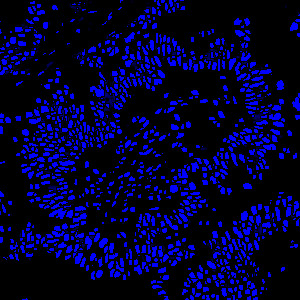

Tissue stained with DAPI

Identification and segmentation of individual nuclei is of interest in many applications. Nuclei can be difficult to detect accurately and precisely across different images using traditional image analysis with feature engineering. This APP utilizes artificial intelligence (AI) for automatic nuclear segmentation in fluorescence images stained with a family of blue dyes for DNA identification. It consists of a pre-trained deep neural network and the APP is ready for use without additional training.

The APP was trained using 41,000 annotated nuclei from DAPI stained tissue. The architectural structure of the network is a U-Net which is popular for medical image segmentation. The neural network uses a cascade of layers of nonlinear processing units for feature extraction and transformation, with each successive layer using the output from the previous layers as input. U-Net uses an encoder-decoder structure with a contracting path and an expansive path. For more information of the network architecture, see [1].

Tissue must be labeled with a blue fluorescent dye for DNA staining such as DAPI, Hoechst or Iridium such that all nuclei are labeled.